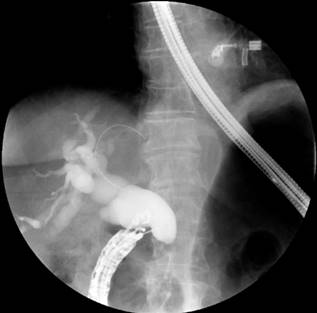

Con los hallazgos descritos se decidió el manejo paliativo y se llevó a CPRE con la intención de realizar una derivación biliar con stent; se encontró la papila distorsionada con retracción local de las paredes duodenales y se logró la canulación de la vía biliar distal, pero fue fallida para la vía biliar proximal. Entonces, se realizó la derivación biliodigestiva guiada por USE, en la que se encontró una infiltración neoplásica de la papila duodenal que impide su canulación y la cabeza del páncreas tenía una lesión hipoecoica heterogénea de 23 mm de diámetro con una dilatación retrógrada de la vía biliar hasta 18 mm (Figura 4). Se realizó una punción inicial de la masa para el estudio histológico y, posteriormente, de la vía biliar transduodenal con una aguja de 19 Fr, avanzando la guía hidrofílica 0,035; la dilatación se realizó con un balón dilatador biliar bajo control fluoroscópico y la posterior colocación del stent biliar metálico completamente cubierto de 10 x 80 mm, el cual se liberó bajo control endoscópico y fluoroscópico con una adecuada apertura y drenaje del medio de contraste y de bilis clara, sin complicaciones posteriores (Figuras 5 y 6). El reporte de la citología obtenida por endosonografía confirmó el compromiso por adenocarcinoma. A los 2 meses se le realizó control de bilirrubina total en 2,42 mg/dL; directa, en 1,85 mg/dL; e indirecta, en 0,58 mg/dL (Figura 7). La paciente continuó el manejo con oncología y cuidados paliativos.